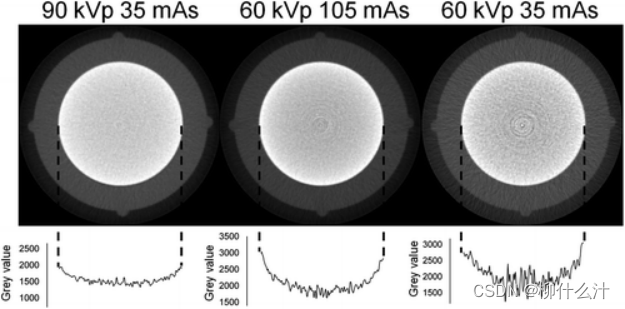

CBCT中的光束硬化。顶部:包含铝制圆柱体的小尺寸幻影的轴向切片。底部:显示由于光束硬化而沿着圆柱体直径的灰色数值变化的曲线图。更高的kVp可以减少光束硬化;mAs的变化会影响噪声,但不会影响光束硬化。